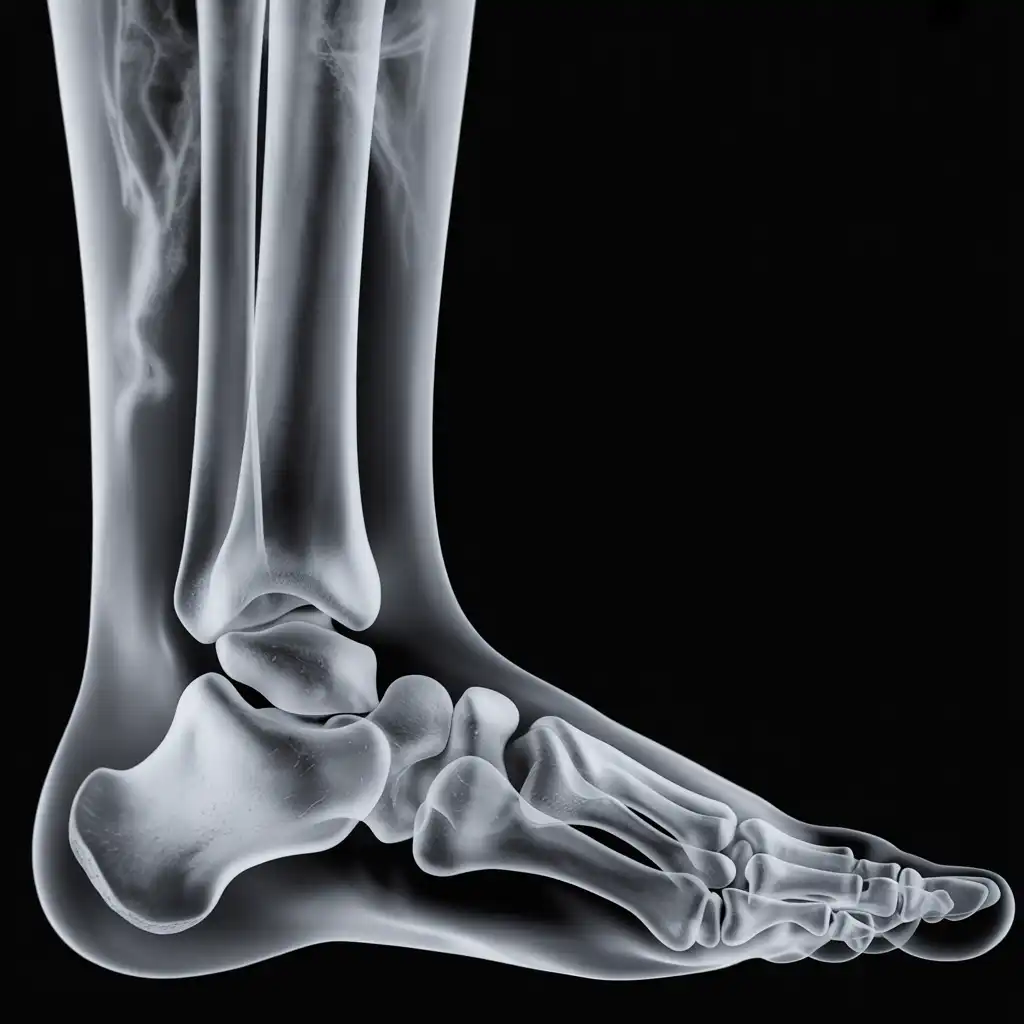

Una lastra a domicilio è una radiografia eseguita direttamente a casa del paziente, grazie all’intervento di un tecnico sanitario qualificato dotato di apparecchiatura digitale portatile.

L’esame viene effettuato sul posto, senza necessità di spostare la persona dal letto o dalla poltrona, e garantisce una qualità diagnostica paragonabile a quella di un reparto ospedaliero.

Una volta acquisite, le immagini vengono trasmesse al medico radiologo, che le analizza e redige il referto in tempi brevi.